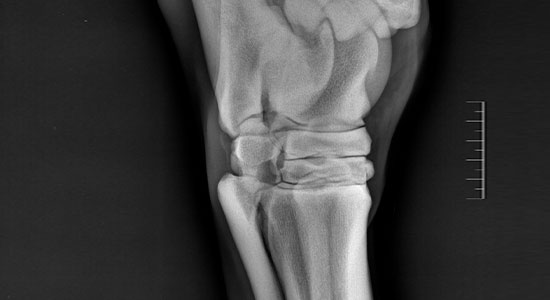

Bei einer Ankaufsuntersuchung wird eine klinische Untersuchung durchgeführt und das Exterieur des Pferdes hinsichtlich zahlreicher Faktoren eingehend untersucht und anschließend beurteilt.